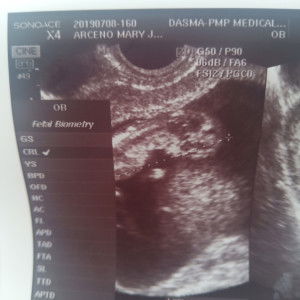

expecting baby girl